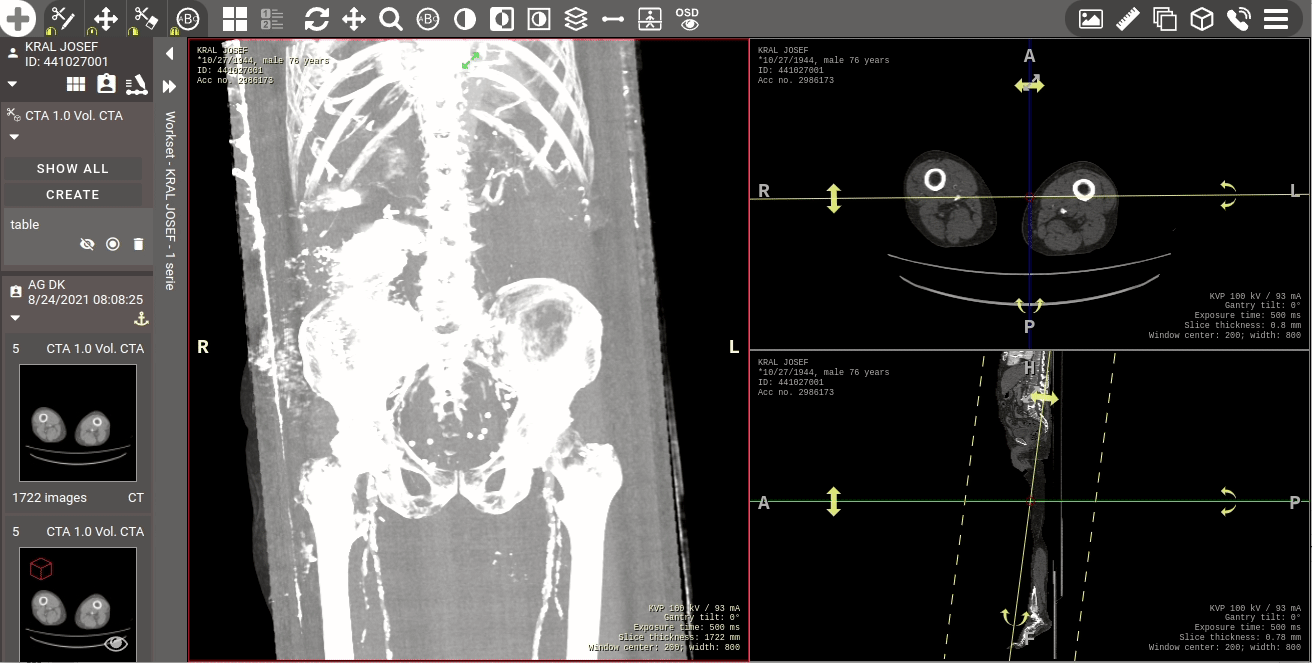

Tato nová verze přináší citelné zrychlení práce v prostředí DICOM prohlížeče, kdy došlo až ke 4násobnému urychlení načítání větších snímků do mezipaměti prohlížeče a rychlejšímu dotahování dat ze serveru do pracovní stanice. K urychlení došlo také v případě využívání Hanging protokolů, kdy došlo k jejich optimalizaci vyhodnocování a aplikování na studii a můžete tak očekávat až 10násobné urychlení zobrazení studií s aplikovaným Hanging protokolem oproti předchozí verzi a to i s rozšířením podporovaných funkcí Hanging protokolů.